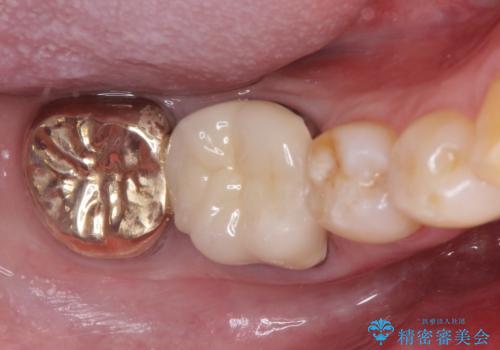

虫歯の治療 オールセラミッククラウン

担当医 河口智英